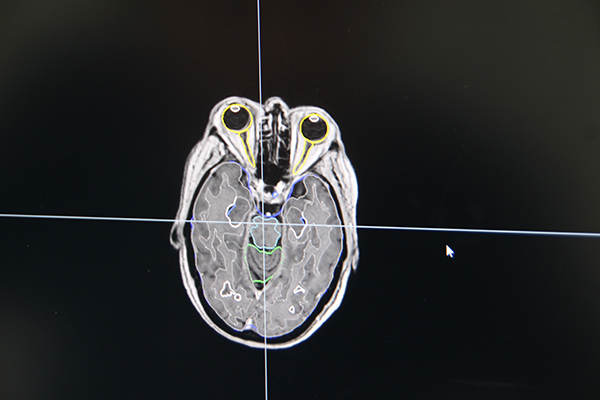

アキュレイプレシジョンの特長の一つが,頭蓋内,頭頸部,男性骨盤内を対象にした“AutoSegmentation”機能である。従来は,重要臓器の輪郭作成に膨大な時間を要していたが,AutoSegmentationではGPUを応用することで,計画用CT画像を取り込むと設定された重要臓器の輪郭を自動で囲むことができる。例えば,頭部では1分程度で輪郭作成が可能で,治療計画の作業時間が大幅に短縮可能となる。

重要臓器を自動で抽出する“AutoSegmentation”機能

小児に対する全身照射(TBI)の治療計画画面